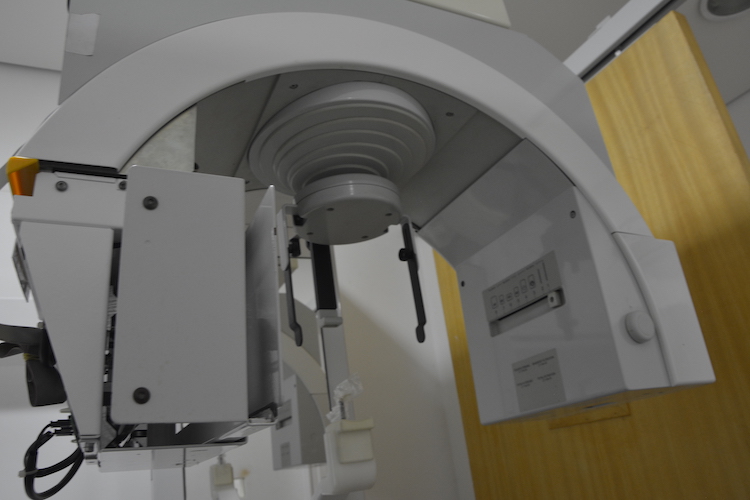

ConheçaInfra Estrutura Clínica